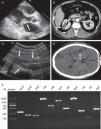

During the next two days, echocardiography revealed large vegetation on the anterior mitral valve leaflet (3cm×3cm) with moderate mitral valve regurgitation (Fig. 1A) Spiral computed tomography (CT) showed renal and splenic infarction (Fig. 1B). CT scans of the brain demonstrated multiple low-density bilateral lesions of the temporal lobes, right parietal lobe and occipital lobe, suggestive of cerebral embolism. Preliminary blood cultures grew S. aureus susceptible to ciprofloxacin, rifampicin, linezolid, vancomycin, tetracycline, sulfamethoxazole, levofloxacin and fosfomycin but resistant to penicillin, oxacillin, clindamycin, cefazolin, cefoxitin, cefuroxime, and erythromycin, as determined on the basis of CLSI disc diffusion standards. A diagnosis of acute infective endocarditis with systemic embolism caused by CA-MRSA was thus considered. Because of his impaired renal function and bacterial susceptibility profile, the patient was treated with intravenous linezolid (600mg q12h) and fosfomycin (8.0g q12h).

Infective endocarditis complicating systemic embolism (the arrows indicate areas of interest) and detection of key genes. (A) Color Doppler echocardiography showing the vegetation attached to the anterior mitral valve leaflet. (B) Spiral computed tomography showing renal infarction. (C) Echocardiographic examination showing embolization of the right common iliac artery and right internal and external iliac arteries. (D) Computed tomography of the brain showing multiple low-density lesions. (E). Detection of antimicrobial genes, virulence-related genes and adhesion genes by PCR amplification. Lane 1, molecular weight marker; lane 2, mecA; lane 3, ermC; lane 4, blaZ; lane 5, clfA; lane 6, clfB; lane 7, icaA; lane 8, efb; lane 9, fnbA; lane 10, hlb; lane 11, hld; lane 12, hlg2.

On day 10, his clinical status worsened with episodes of tachypnea, pink frothy sputum and oxygen saturation (SpO2) decreased rapidly to 83% with ventilator support. Furthermore, renal function deteriorated, oliguria and right lower extremity tissue necrosis appeared. Embolization of the right common iliac artery and right internal and external iliac arteries was seen on echocardiography (Fig. 1C). He subsequently developed a coma with a Glasgow Coma Scale (GCS) score of 6. His clinical condition deteriorated such that he was transferred to the ICU, and replacement of the mitral valve was accomplished with a 29-mm Carbomedics mechanical valve. Considering the presence of coma and fever (39.8°C) postoperatively, brain CT was obtained and showed multiple low-density lesions in temporal lobes, right parietal lobe, and occipital lobe, suggestive of cerebral embolism (Fig. 1D). Levofloxacin (0.75g qd) was added to his antibiotic regimen. After 10 days of intravenous antibiotics, the patient regained consciousness (GCS score of 9) and made a good clinical recovery. On day 35, he was transferred to a secondary hospital, and linezolid therapy was continued for eight weeks. He recovered uneventfully and was well at the last follow-up in November 2013.

The CA-MRSA isolate was typed as sequence type (ST) 630 SCCmecV with spa-type t4549, agrI/IV and was PVL-negative. We confirmed the presence of mecA, ermC and blaZ genes by PCR and sequencing. The genome of the MRSA isolate encoded three hemolysin genes (hlb, hld and hlg2) and five adhesion genes (clfA, clfB, fnbA, efb and icaA) (Fig. 1E).